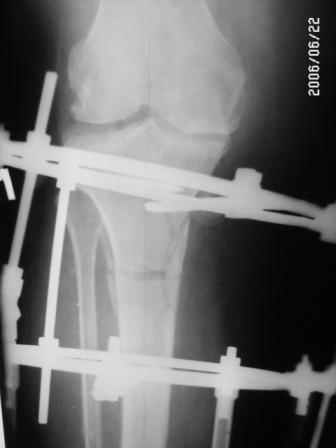

Глядя на снимки, кроме оперативного лечения в голову ничего не приходит. Хотя бы корригирующая кортикотомия б/б кости с минимальной внешней фиксацией. Высылаю пример.

На последнем фото внешний вид больной на завершающем этапе лечения (30 сутки) с трансформацией АВФ из гибридного в стержневой. Боль уходит сразу после операции. При данной Р-картине консервативно показано применение только обезболивающих препаратов - трамадол до 3 мес. по 100-200 мг в сутки, возможно внутрисуставное введение морфина 1,0 мл. При скрыто протекающем синовиите добавляются НПВС. Кроме того, должна помочь остеорефлексотерапия - в/костной иглой пункция проксимального метафиза б/б кости с введением 1,0-0,5 мл. физ.р-ра или новокаина. Возможе и вариант расширенного вмешательства по Беку: узким долотом через кожный разрез в 3-4 мм делается «прокол» кортикального слоя и маятникообразными движениями разрушается костный мозг. Боль проходит практически всегда и надолго.

Моим примером, я хотел продемонстрировать малотравматичный вариант коррекции механической оси голени, который дает достаточно длительный положительный эффект и является, насколько я знаю, альтернативой ЭП.